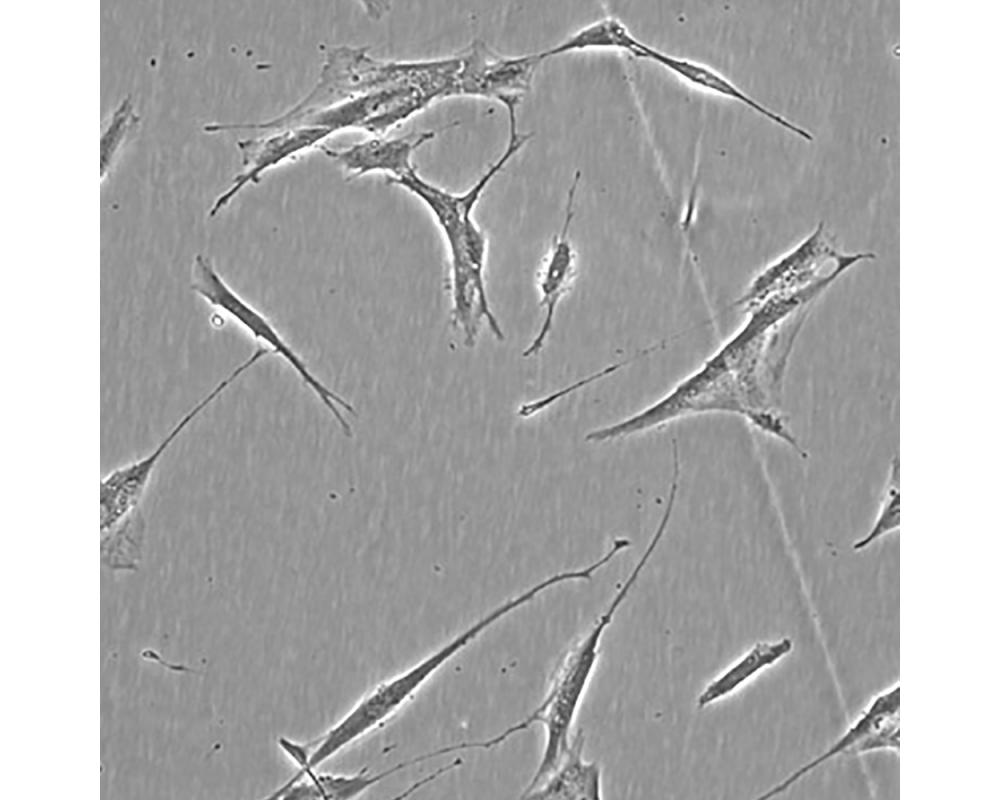

產(chǎn)品名稱 Hs 606.T

中文名稱 人乳腺癌細(xì)胞

組織來源 乳腺癌;女性

生長特性 貼壁